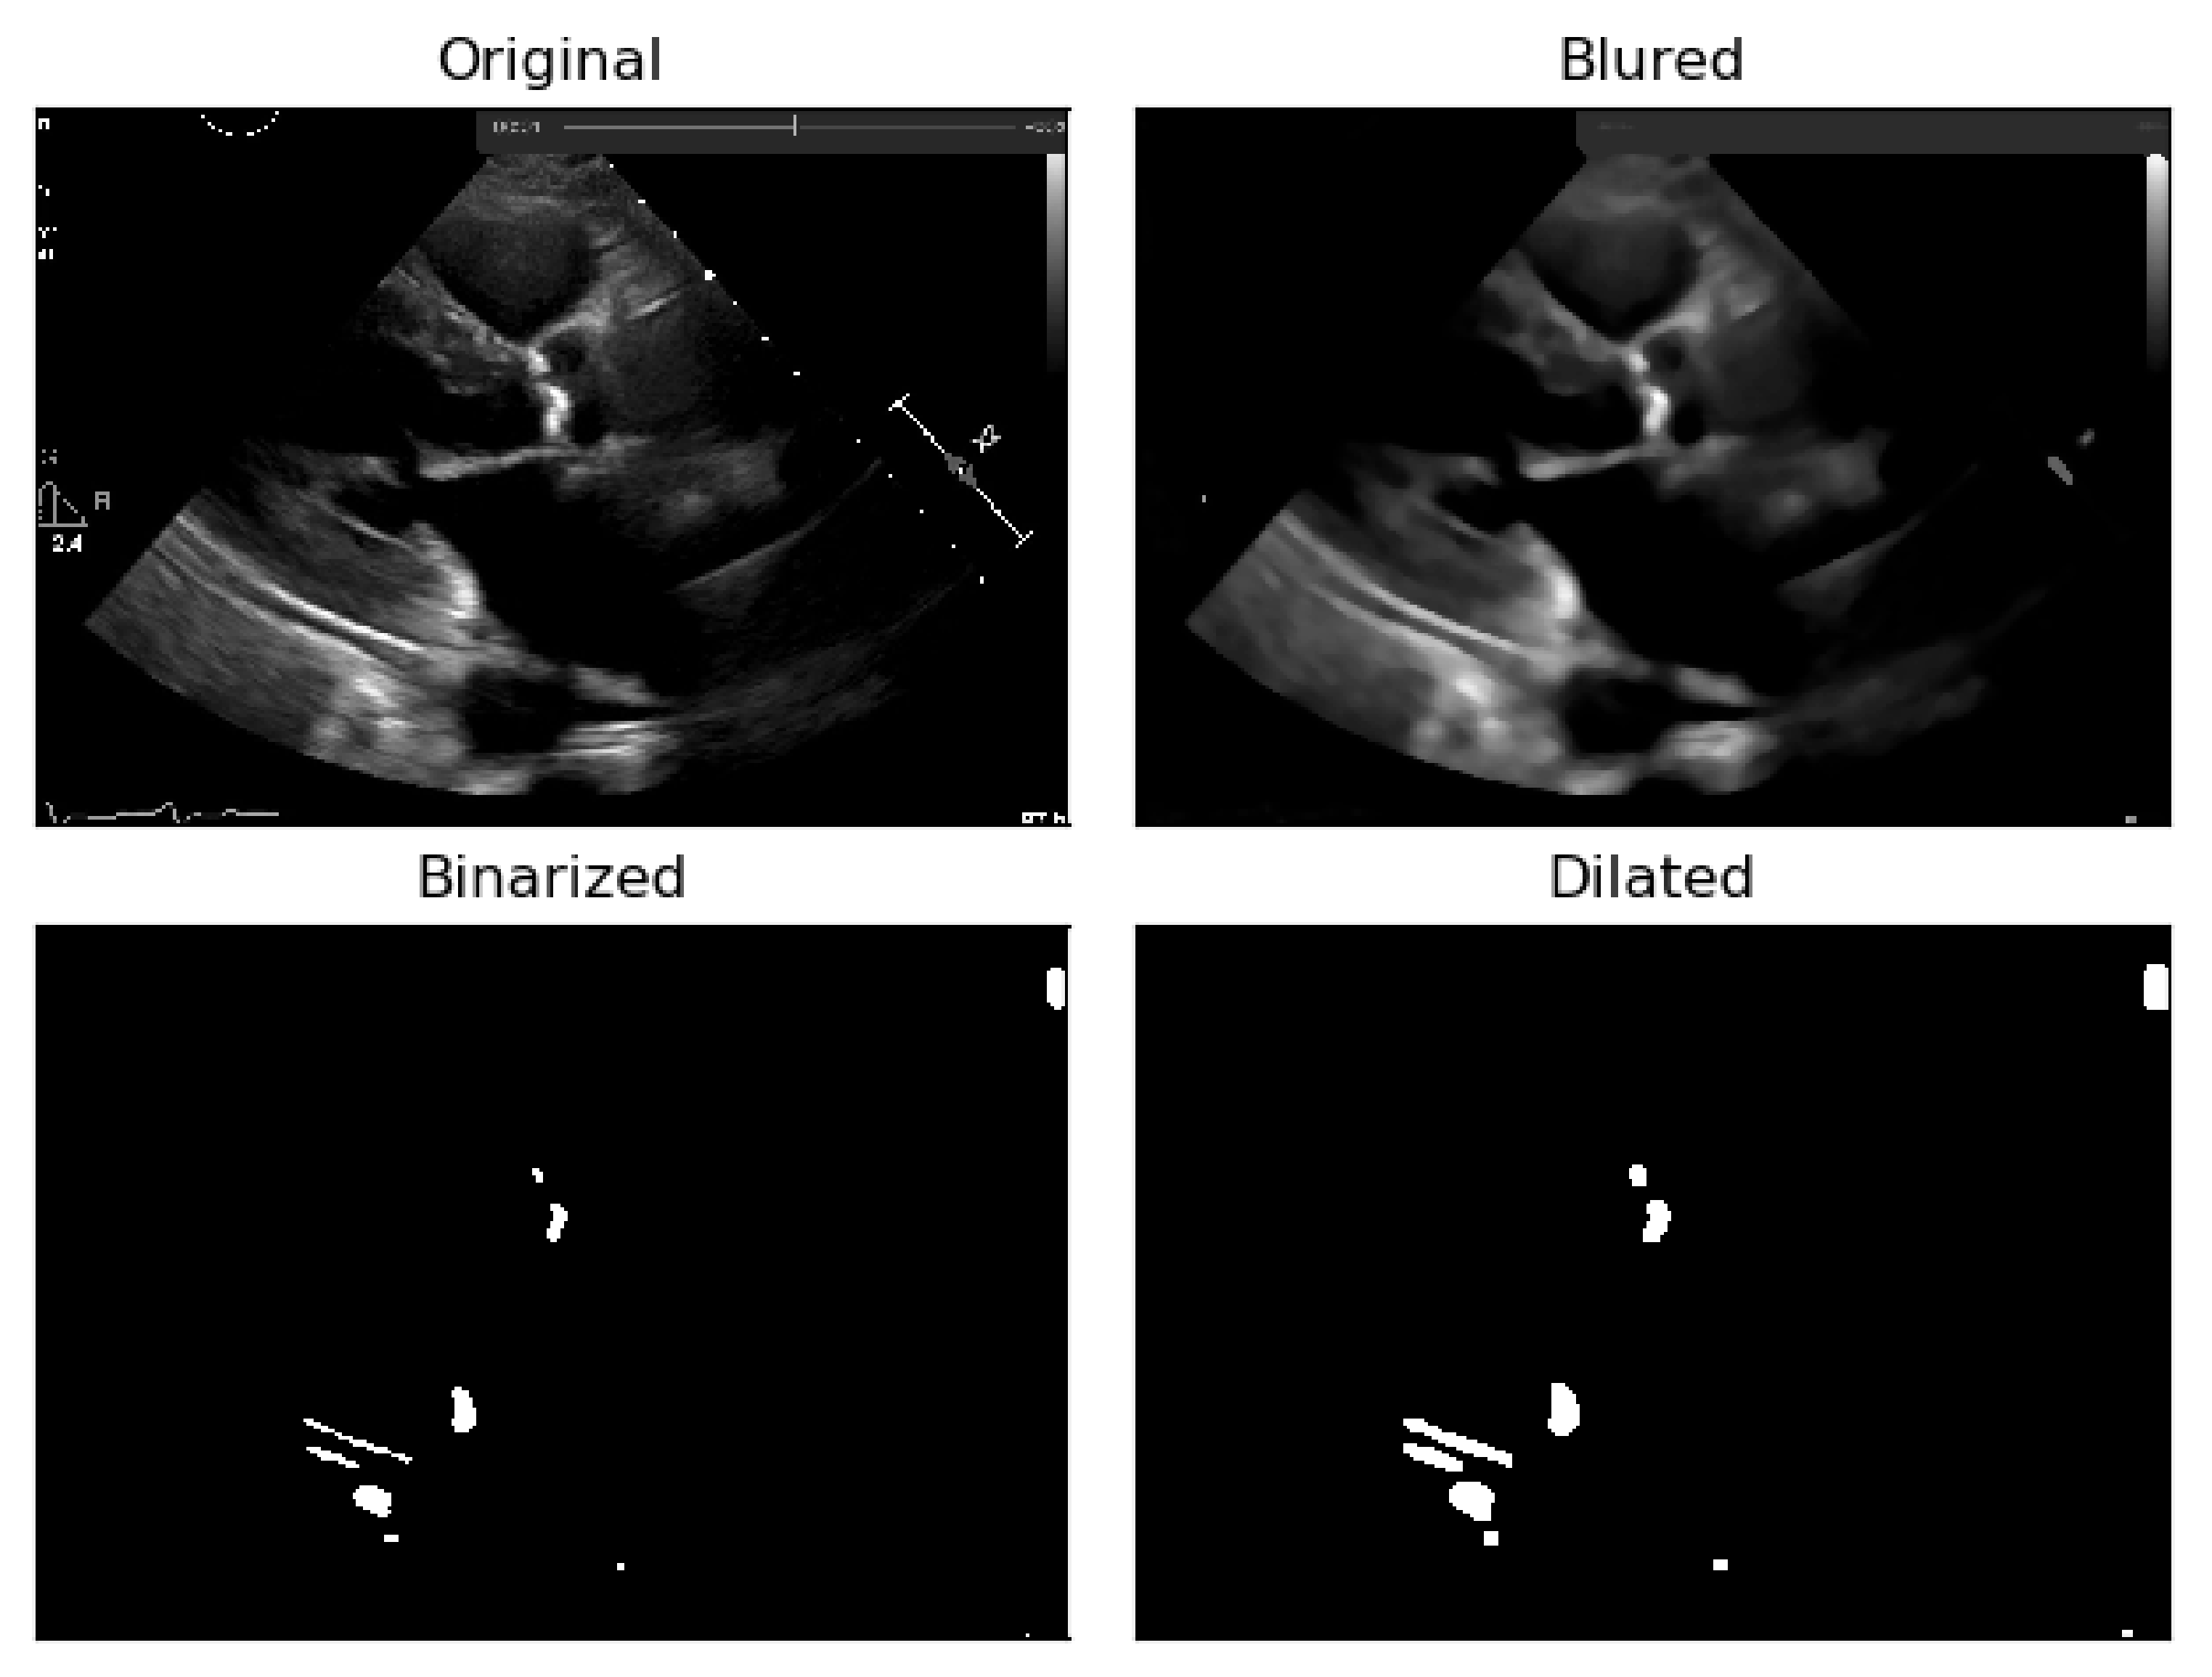

To deal with some natural constraints in terms of noise that characterize echocardiography imaging, particularly the process of sampling still images from the echocardiography video, different blurring treatments were performed to clean some of the image’s noise due to the echocardiography’s motion. Blurring an image will average rapid changes in the different pixel intensities, and this corresponds to a low-pass filter applied to the image [23], which removes noise while leaving the majority of the image structures still present in the image as depicted in Figure 4.

As it can be seen from Figure 4, when the Blur = 11 (experimentally adjusted with trial and error)), it can be easily identified, visually, in the regions where there is a presence of calcium (identified by the red circles). On this operation the central element of the image is replaced by the median of all the pixels in the kernel region, where the 11 means that it takes into consideration a kernel of 11 by 11.

To the resulting images of this blurring phase, a binarization operation with a fixed pixel threshold value of 160 was produced, experimentally obtained by analyzing 48 cases of echocardiography images, where 255 corresponds to calcium, as seen in Figure 5. This initial approach of a using a fixed threshold is not sufficient for our problem at hand, since our images’ brightness may vary, given different data collection conditions. To tackle this issue, an adaptive binarization technique has to be performed, which will be further explained.

In Figure 5, it is noticeable that when the blurring parameter increases from 5 to 11, we get a cleaner image (without small white dots—noise). However, we can also notice that in the region of interest (marked with red circles), when the blur increases, we lose pixels, since the region gets smaller. To mitigate this, a mask dilation operator was applied to each region of interest.

As shown Figure 6, the pixels lost in the blurring phase can be recovered by applying the dilation mask to the regions of interest in the image.

Figure 4. Echocardiography image with four levels of blurring applied—the red circle represents our ROI where the aortic valve is located.

Figure 5. Binarization of an echocardiography image, for each size of the kernel parameter applied—The red circle represents our ROI (aortic valve).

Figure 6. Application of the dilation mask to the regions of interest of the image, in order to recover the pixels lost in the blurring phase.